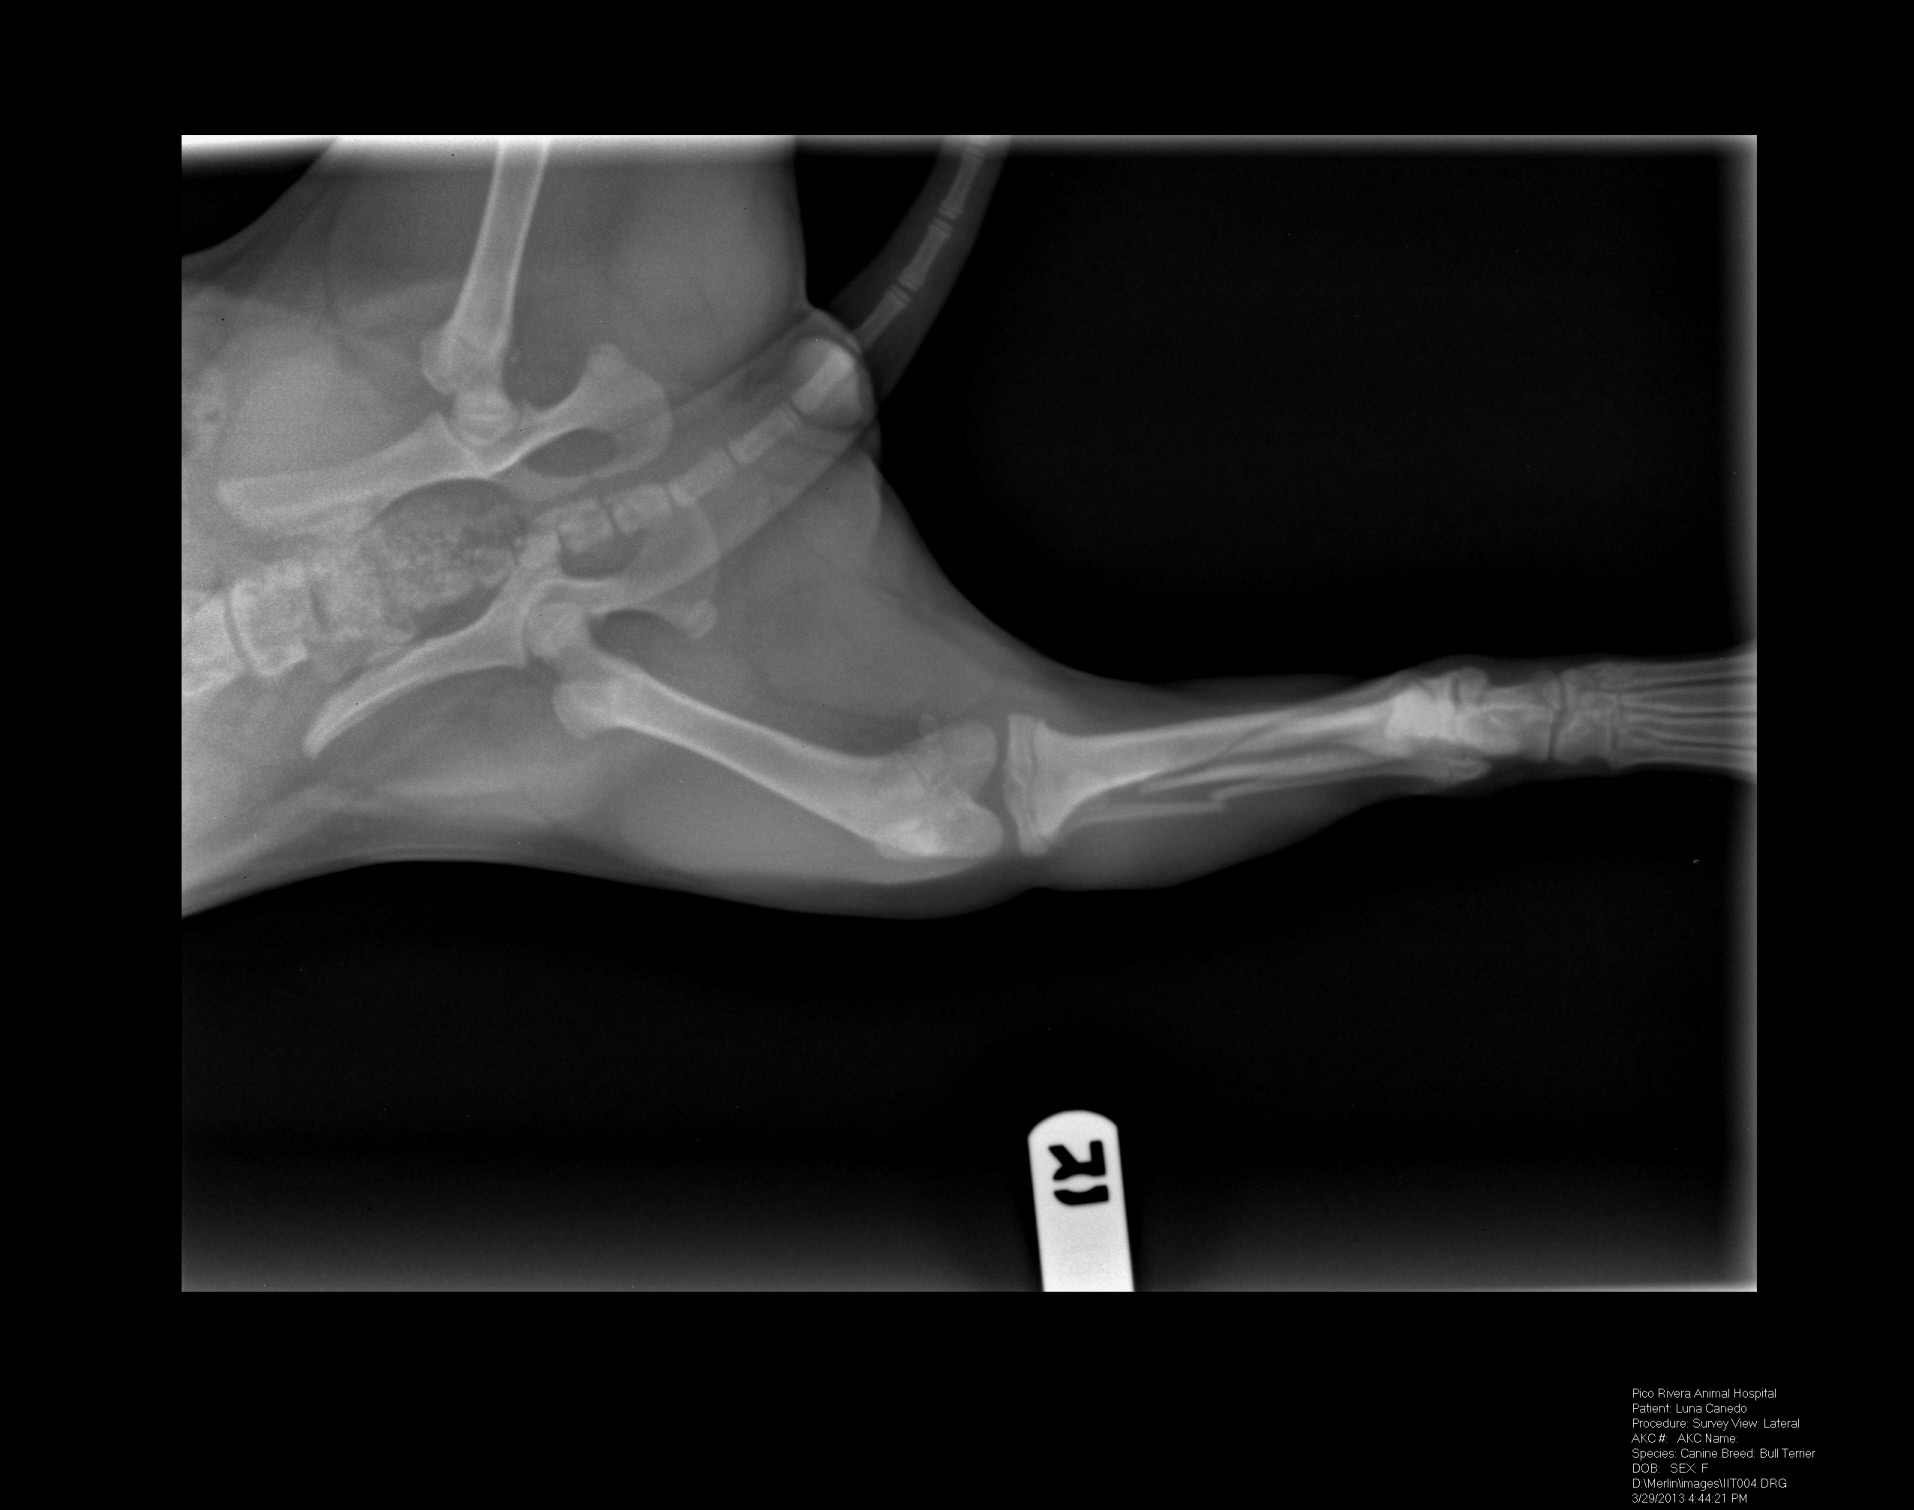

help!!!!!!!!!!!! i think my luna broke her leg!!!!!